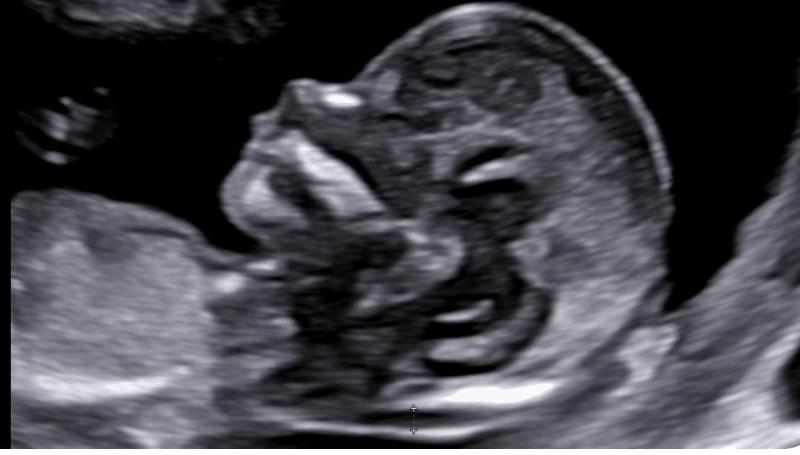

Lo Studio Medico Ginecologico della Dott.ssa Francesca Calonzi è situato a Viterbo in Largo Nagni 15. Lo studio completamente rinnovato è dotato di sistemi diagnostici di ultima generazione e si avvale della collaborazione di molteplici medici specialisti e figure paramediche, per offrire un servizio completo di diagnosi e cura nei vari ambiti. La Dott.ssa Calonzi, specialista in Ginecologia e Ostetricia si è laureata e specializzata presso lUniversità degli studi di Roma Tor Vergata. Dal 2017 esercita presso lospedale Santa Rosa di Viterbo e offre assistenza nella donna in gravidanza sia nelle gravidanze fisiologiche che nellambito della patologia ostetrica, dalla fase preconcezionale al postpartum. Presso lo studio ginecologico inoltre è possibile effettuare visite volte a valutare il benessere generale della donna dalla fase adolescenziale alla menopausa.